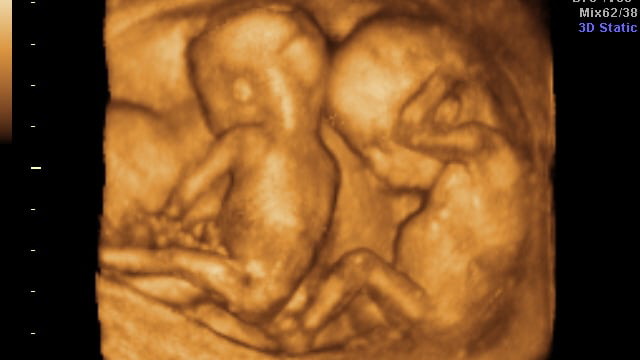

«Egizder bolatynyn bilgende shoshydym. Júktilik men úshin aýyr boldy. Búıregim aýyrǵandyqtan, olardy kóterý qıyn boldy. Bosanǵan kezde de qatty qınaldym. Balalarym ýaqytynan buryn dúnıege keldi. Dárigerler ulymnyń aman qalýy ekitalaı dedi. Jansaqtaý bóliminde bir jarym aı jattyq. Aýrýhanadan shyqtyq, Artýr ulym aman qaldy. Qazir eki balam da eki jasta. Qyzym sóıleıdi, al ulym bolsa bir nárseni birneshe ret aıtqanda ǵana estip, keıbir nárselerdi túsinbeı júrdi. Dárigerlerge baryp qaralǵan soń, ulymnyń estý qabileti nashar ekeni anyqtaldy. Emdelip júrdik. Sol ýaqytta ulym qaıta aýyryp qalyp, estýi tipti nasharlap ketti. Arnaıy appart quralyn satyp alyp endi sonyń kómegimen Artýr jaqsy estıtin boldy»-deıdi eki balanyń anasy.